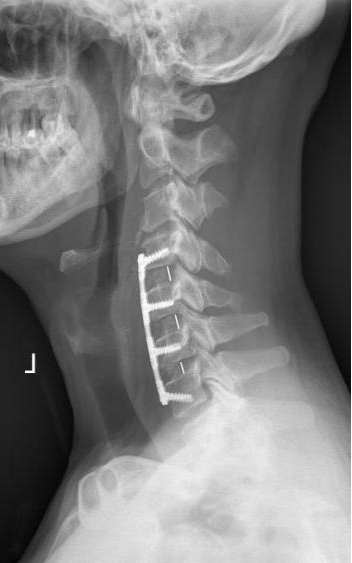

在通过沟通后,骨病中心主任袁毅团队为患者施行显微镜辅助下颈椎前路颈椎间盘切除+椎间植骨融合内固定术(ACDF)。术中在显微镜的辅助下,清楚显露解剖结构,彻底切除椎间盘、骨赘、减压椎间孔,切除后纵韧带,解除脊髓神经压迫,术中出血约20ml。

术后,无血肿压迫、脑脊液漏、感染等并发症发生,术后1周顺利康复出院。

手术步骤包括减压和重建稳定两大部分。在切除椎间盘组织后,采用显微镜辅助,使手术视野更清晰,手术过程中采用超声骨刀动力系统、磨钻、刮匙等工具切除椎体后方上下缘及钩突后方骨赘,扩大椎间孔,再切除钙化的后纵韧带、充分减压脊髓神经。然后在椎体间植入合适大小的椎间融合器(Cage)恢复椎间隙高度、安装前路钛板,重建椎体间稳定性。